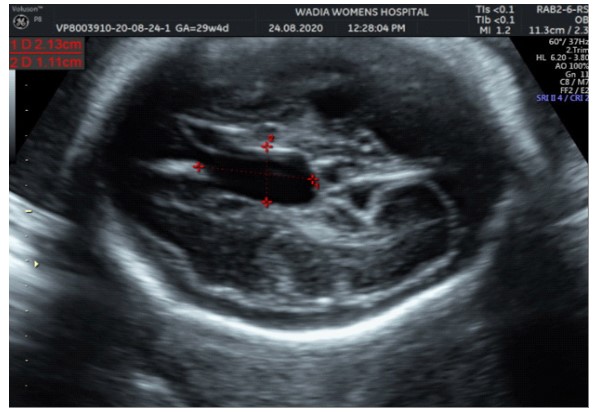

In the third conception during the COVID-19 pandemic, the couple presented to us in the third trimester. Anomaly screening ultrasound at 18 weeks done elsewhere was unremarkable, but subsequent scan done at our institute at 29 weeks was suggestive of fetal biometry corresponding to 26 weeks, head circumference below 1st centile, composite growth along 3rd centile. The fetus had microcephaly and sloping forehead; head circumference measured 241 mm (less than 1st centile for gestational age) (Figure 1). Transcerebellar diameter measured 23.6 mm (<1st centile) with vermis spared suggestive of cerebellar hypoplasia (Figure 2). The Cavum Septum Pellucidum (CSP) was enlarged measuring 22 mm x 10 mm (Figure 3). Additional ultrasound findings were corpus callosum agenesis, kinked thalami, widened subdural spaces and right club foot (Figure 4). The ultrasound differentials were pontocerebellar hypoplasia or Walker Warburg syndrome.